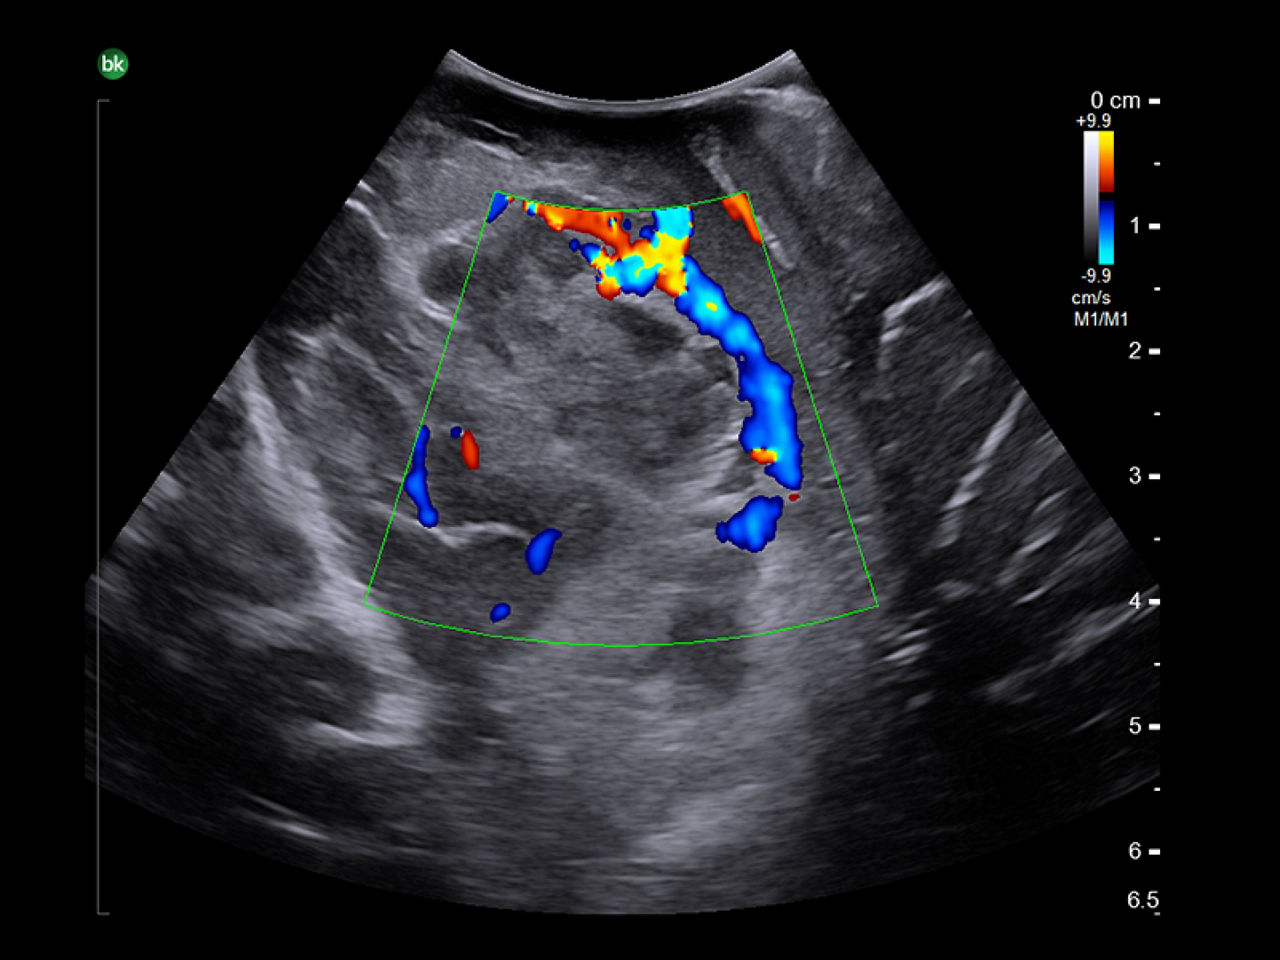

Neurovascular

Shorten operative time with intraoperative ultrasound³. Use intraoperative ultrasound during surgery to: locate AVM nidus and identify feeding arteries with color Doppler, assess for resection of AVMs⁴, identify associated hematoma⁵, and visualize preoperative embolization (e.g. Onyx®).